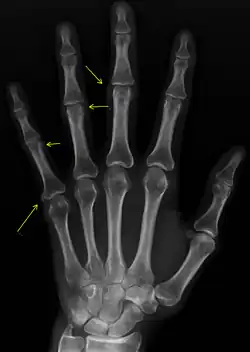

CREST syndrome (calcinosis and sclerodactyly)

X-ray of subtle calcifications in CREST syndrome

Calcinosis

CREST causes thickening and tightening of the skin with deposition of calcific nodules ("calcinosis").